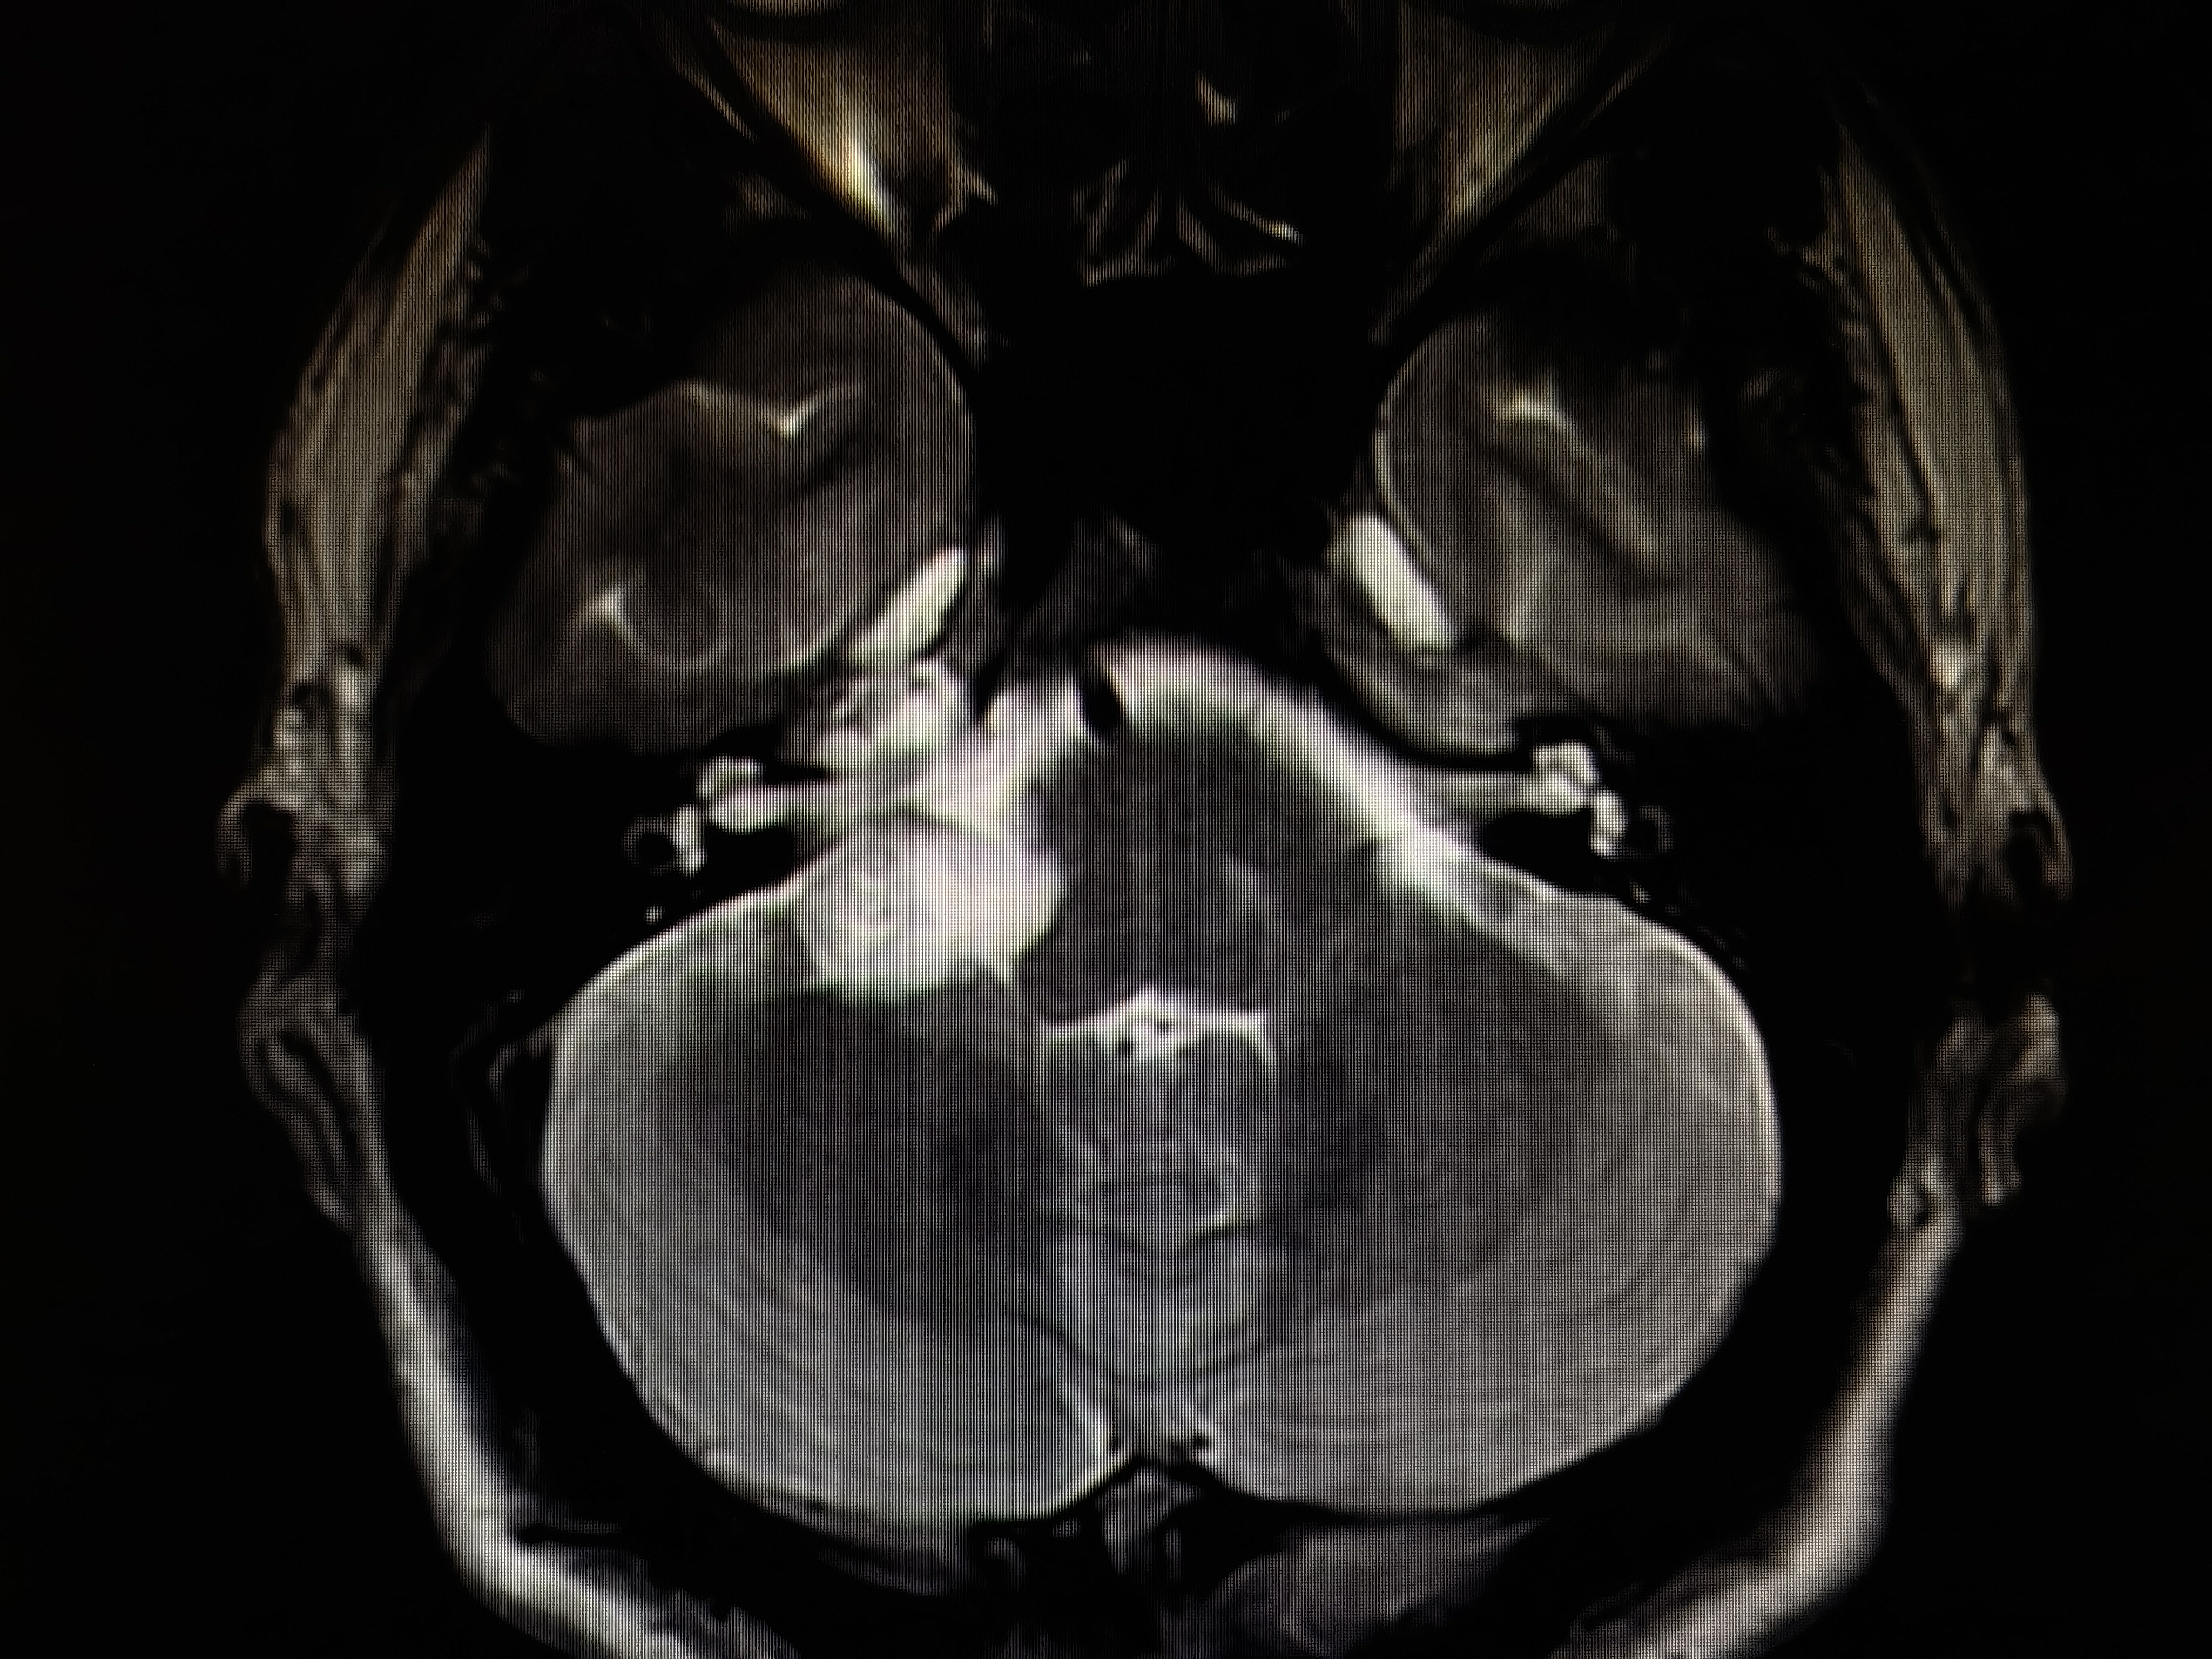

术前磁共振